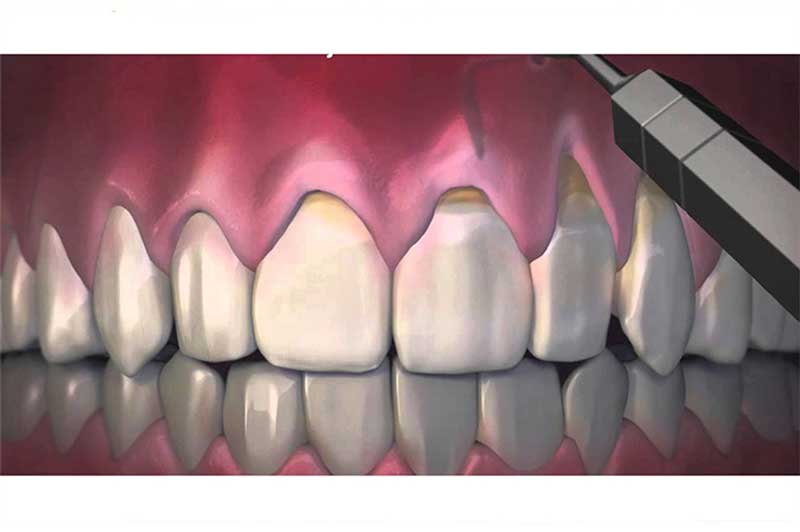

معمولا بیماری مانند التهاب لثه در نهایت منجر به تحلیل و از بین رفتن لثه ها و در مجموع از دست دادن دندان ها می شود، در این شرایط معمولا بیماران نیاز به جراحی لثه داشته و در اکثر موارد نیز التهابات موجود در لثه به دلیل سلامت و بهداشت دهانی پایین و جرم های موجود در دندان می باشد.

التهاب لثه از جمله بیماری های خفیف لثه به حساب می آید که دندانپزشک در صورت وجود علائمی مانند قرمزی، ورم و حتی خونریزی مجبور به جراحی لثه در ونک می شود. به یاد داشته باشید که درمان اولیه بیماری های لثه بهتر از مراجعه دیر هنگام و از دست رفتن لثه و دندان ها است با این حساب به شما توصیه می کنیم در صورت بروز هرگونه علائمی در لثه های خود به فوریت به دندانپزشک و متخصص مراجعه کنید تا در صورت نیاز جراحی لثه انجام شود و سلامت دهان و دندان شما در اولویت قرار خواهد گرفت.

در بعضی موارد در محل اتصال بین دندان و لثه به علت تجمع باکتری و بقایای مواد غذایی فاصله ای ایجاد می شود که موجب التهاب، بوی بد دهان و خونریزی لثه می شود. به کمک این جراحی بافتهای ملتهب و بقایای مواد غذایی و باکتری ها از لثه حذف شده و دوباره اتصال بین دندان و لثه اطراف آن برقرار می شود.